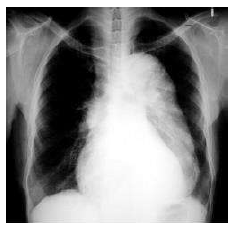

Um homem de 62 anos de idade, com antecedentes de hipertensão e diabetes, procurou o pronto-socorro com relato de dor torácica intensa, lancinante, irradiada para o dorso havia uma hora. No exame, o paciente apresentava fácies de dor, frequência cardíaca de 85 bpm e pressão arterial de 160 mmHg × 80 mmHg. Inicialmente, ele foi submetido a uma radiografia de tórax, cujo resultado está reproduzido a seguir.

Após o exame inicial, a principal hipótese diagnóstica foi confirmada pela angiotomografia.

Nesse caso clínico, a conduta medicamentosa essencial na sala de emergência deve ser composta de